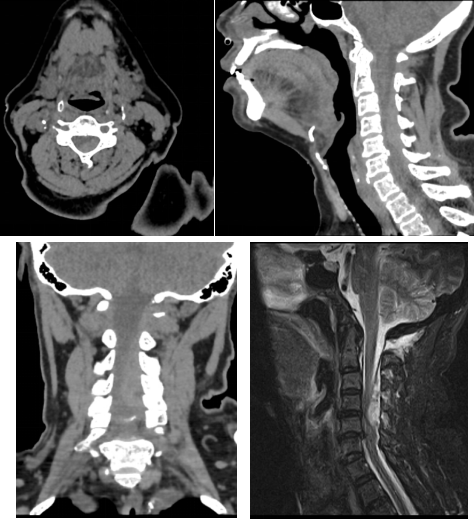

術(shù)前頸椎CT和磁共振:可見明顯血腫占位

通訊員符得紅報(bào)道:近日,63歲譚女士因“頸部疼痛伴左側(cè)肢體癱瘓2小時(shí)”聯(lián)系120后被送至我院脊柱外科,完善頸椎CT、磁共振后考慮“頸椎管內(nèi)出血并頸髓損傷”。體查:頸部活動疼痛受限,左側(cè)肢體肌力約Ⅱ級,右側(cè)肢體肌力正常。既往有“高血壓”、“糖尿病”、“心臟病”病史,3年前在外院行“冠脈支架植入”,術(shù)后一直口服“抗凝藥物”抗凝治療。